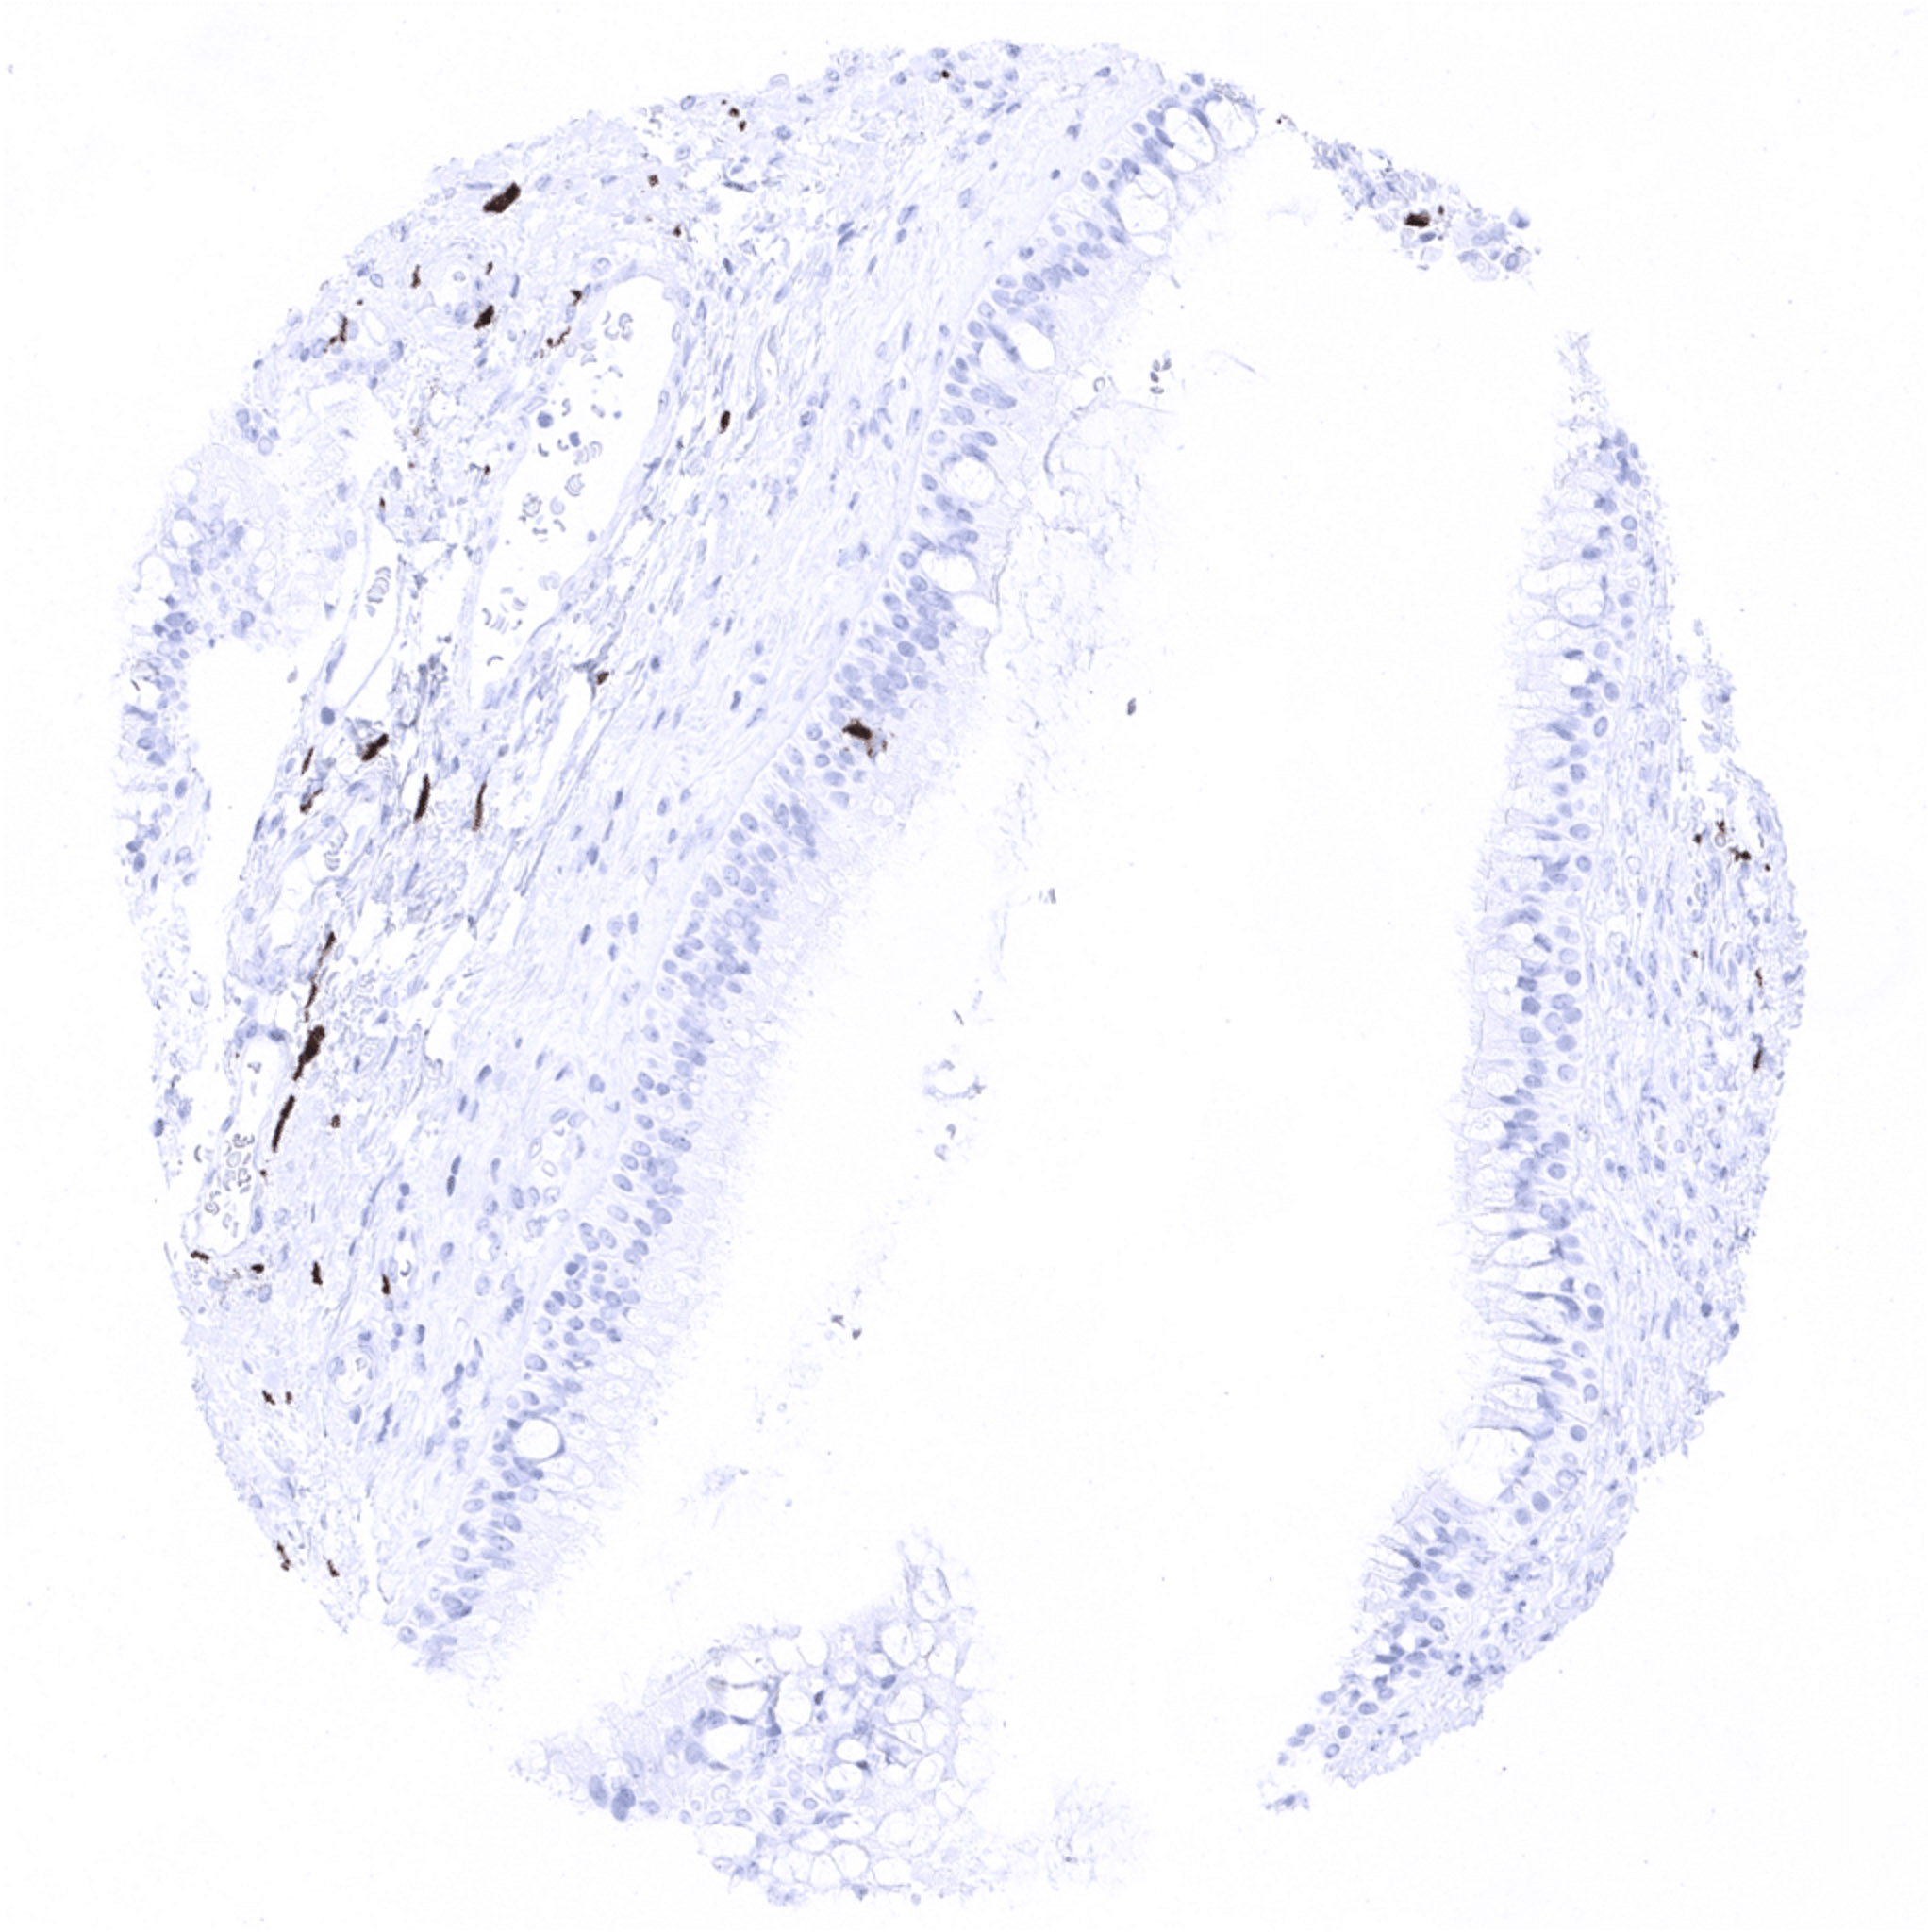

Aorta, media

Appendix, mucosa – Appendix with a multitude of intramucosal S100 beta positive nerve fibres.

Appendix, muscular wall – S100 beta positive nerve fibres are abundant in the muscular wall of the appendix.